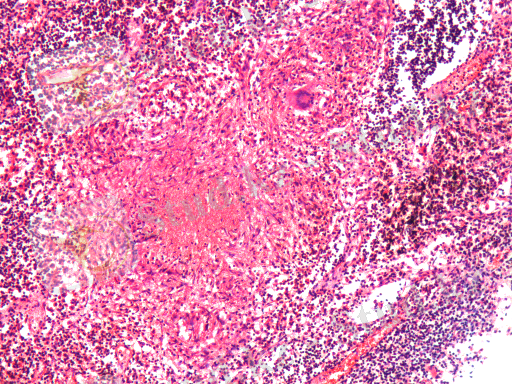

Кеуде ішілік лимфа түйіндерінде (бифуркациялық және бронхопульмоналдық) туберкулездік лимфадениттер дамыды. Олардың стромасында гиперпластикалық үрдістер, субкортикалдық аймақтар мен милы қабатының синустарында макрофагалды реакция, ретикулярлы жасушалардың пролиферациясы байқалды. Барлық көру аймақтарында ортасында казеозды некрозы бар эпителиодты-жасушалық, Пирогов-Лангханс типті алып жасушалардан тұратын туберкулездік гранулемалар анықталды (4 сурет) .

3-ші сурет. Казеозды-некротикалық 4-ші сурет. Лимфа түйіндеріндегі

бронхит, бронх қабырғасының казеозды туберкулездік гранулемалар.

еруі. Гематоксилин және эозин бояуы. Гематоксилин және эозин бояуы.

Үлкейту х 200. Үлкейту х 200.